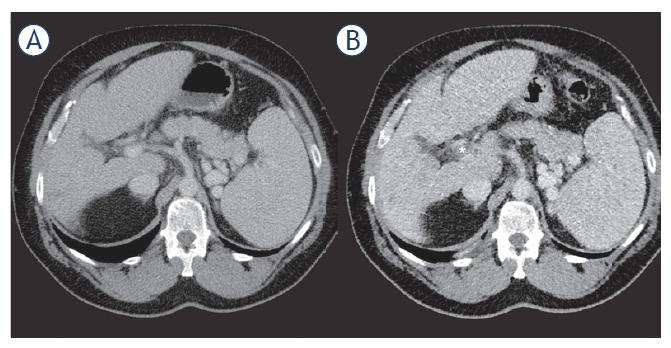

Figure 2